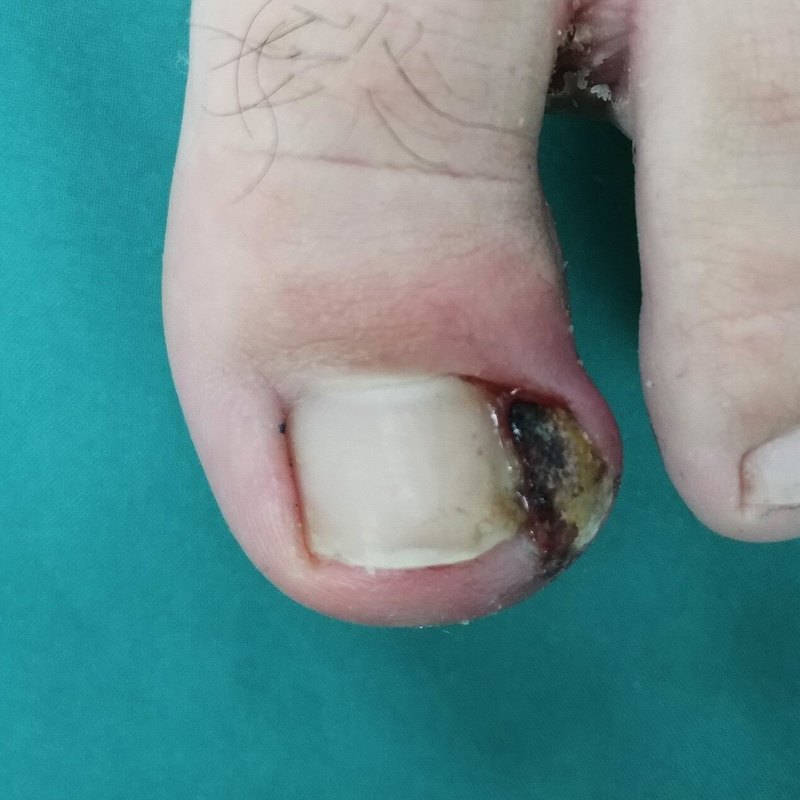

嵌甲是趾甲板外緣或內(nèi)緣或側(cè)角嵌入甲溝皮膚,引起局部疼痛,當(dāng)甲緣穿破皮膚時細(xì)菌侵入可導(dǎo)致甲溝炎。修剪趾甲不當(dāng)為其中的原因之一。臨床上,將甲溝炎分為三期:1期(炎癥期):表現(xiàn)為患甲側(cè)方甲皺襞出現(xiàn)輕度紅腫、疼痛。2期(膿腫期):由炎癥期發(fā)展而來,此時局部紅腫、多汗、壓痛加劇,兩側(cè)甲皺襞腫脹高出甲板側(cè)緣,且開始有滲液流出。流出液為稀薄、粘稠的血清樣分泌物,引流不暢會引起感染迅速形成,分泌物變?yōu)槟撔圆⒂谐粑?。患者此時行走困難,幾乎不能穿鞋。3期(肉芽形成期):肉芽組織覆蓋于側(cè)方甲皺襞,妨礙引流物的流出。若患者不能及時治療,增生的甲上皮將覆蓋肉芽邊緣,若引流不暢,使炎癥向深部蔓延擴(kuò)散。(一)手術(shù)方法(1)對1期(炎癥期)患者治療:將甲板側(cè)緣自側(cè)方甲皺襞皮膚內(nèi)部分掀起,用不吸水的棉墊塞入甲角處,將趾甲輕輕墊起,涂抹百多邦軟膏,一般2~3周取得滿意效果。(2)對2期(膿腫期)和3期(肉芽形成期)患者治療:建議手術(shù)治療,采用局麻下保留甲皺襞的部分甲板甲基質(zhì)(甲根)切除術(shù)(如下-左圖),徹底止血,涂抹百多邦,無菌紗布環(huán)形加壓包扎,手術(shù)后48小時內(nèi)一般不需要更換無菌紗布。一般3周左右取得滿意效果(如下-右圖)。(二)手術(shù)風(fēng)險(1)甲溝炎本身就是感染傷口,手術(shù)后傷口感染可能會加重。(2)術(shù)后若處理不當(dāng),嵌甲甲溝炎會復(fù)發(fā)。1、常規(guī)按說明書口服頭孢類或青霉素類抗生素。2、術(shù)后抬高患肢48小時,1周內(nèi)盡量少走路,少活動,避免緊俏的鞋子,建議穿涼鞋或棉拖,以后要穿寬松的鞋。3、每2~3天換藥1次,每次換藥用碘伏和酒精消毒,涂抹百多邦軟膏,殺菌紗布加壓包扎傷口,一般2~4周傷口愈合,取得滿意效果。1、嵌甲是甲溝炎的常見原因,故要穿合適的鞋子,不要使之過緊,以防發(fā)生嵌甲癥。2、正確修剪趾甲,以防修甲不當(dāng)損傷甲緣而引發(fā)甲溝炎。正確的修甲方法是將甲板的遠(yuǎn)側(cè)邊緣剪成直角,以確保趾甲成方形,兩角突出于甲皺襞的遠(yuǎn)端。1、本康復(fù)計劃僅適用于在山東大學(xué)第二醫(yī)院手足外科進(jìn)行手術(shù)治療的甲溝炎患者。2、本康復(fù)計劃最終解釋權(quán)歸山東大學(xué)第二醫(yī)院手足外科。

嵌甲是臨床常見的一種外科疾病,好發(fā)于大拇趾。通俗的解釋就是趾(指)甲長到肉里去了,引起了炎癥和疼痛。主要表現(xiàn)為患側(cè)甲溝的紅腫和疼痛,有時伴有感染流膿,反復(fù)發(fā)作還會導(dǎo)致炎性肉芽組織瘤樣增生。嵌甲雖然算不上大病,但是十趾(指)連心,疼痛發(fā)作時也會嚴(yán)重影響我們的學(xué)習(xí)、工作和生活。嵌甲發(fā)生的原因很多:不適當(dāng)?shù)男藜?,修剪過深或留有甲刺;長期穿尖頭鞋;長跑或踢球等足部負(fù)荷大的運動;遭受踩踏或擠壓等足部外傷;甲癬導(dǎo)致的甲板變形等等。也許因為嵌甲在很多人眼里只是一個小病,所以醫(yī)生也好,患者也罷,很少有人重視這個問題。很多外科醫(yī)生對這類患者的處理,就是開點抗生素軟膏讓病人回去敷用,對于特別嚴(yán)重的嵌甲患者,頂多也就是將患病的趾甲一拔了之。事實上這些方法都無法有效治愈嵌甲,病人往往稍微好了一段時間,等趾甲長長了就會死灰復(fù)燃甚至更加嚴(yán)重。何況拔甲也是一種比較痛苦的治療手段,有的病人因為害怕拔甲而改投足浴店去扦腳,結(jié)果因為消毒不嚴(yán)格而感染了灰指甲,導(dǎo)致問題更加復(fù)雜。事實上對專業(yè)的足外科醫(yī)生來說,嵌甲要根據(jù)不同的病情成都來選擇不同的治療方案。如果只是初次發(fā)病而且炎癥較輕,的確可以通過局敷理療等方法進(jìn)行治療。但對病程很長,反復(fù)發(fā)作的病人,可以根據(jù)具體情況進(jìn)行矯正治療或者手術(shù)治療。甲板矯正術(shù):原理和矯正牙齒相似,利用特殊的內(nèi)帶鋼絲的矯正器,固定于患趾,收緊鋼絲后,通過鋼絲的牽拉逐漸將變形內(nèi)嵌的甲板拉出甲皺襞,從而消除甲板對甲皺襞的刺激損傷,達(dá)到治愈的目的。我們采用德國進(jìn)口的專用矯正器,在小巧舒適的同時還能提供強(qiáng)大的牽拉力,達(dá)到無創(chuàng)治療的效果。甲溝成型術(shù):對于嚴(yán)重的嵌甲患者,通過手術(shù),切除患側(cè)部分甲板、甲床以及炎性增生的甲皺襞,重建甲溝,使甲溝變寬,甲板和甲皺襞互相分離,從而達(dá)到徹底的治療效果。我們經(jīng)過自己不斷的臨床實踐,改進(jìn)手術(shù)方案,將傳統(tǒng)的開放性手術(shù)創(chuàng)面改為封閉性手術(shù)創(chuàng)面,大大減輕了術(shù)后的疼痛和出血,有助于術(shù)后的早期恢復(fù)。嵌甲的分期及治療方法推薦:Ⅰ期,炎癥期,以側(cè)方甲皺襞出現(xiàn)輕度紅腫疼痛為主。治療方法:理療,局敷,抗炎。Ⅱ期,膿腫期,患側(cè)甲皺襞腫脹且高出甲板側(cè)緣,局部有膿性滲出,伴有膿臭。治療方法:先局敷抗炎控制急性感染,然后做無創(chuàng)矯正。Ⅲ期,肉芽腫期,感染進(jìn)入慢性階段,側(cè)方甲皺襞形成炎性肉芽組織并包裹側(cè)方甲板,病情不可自愈,急性感染和慢性炎癥交替發(fā)展。治療方法:急性炎癥得到控制后采用無創(chuàng)矯正或手術(shù)矯正。Ⅳ期,長期病變后,甲板與甲皺襞同時變形,遠(yuǎn)端足趾肥大。治療方法:手術(shù)矯正?佩戴嵌甲矯正器注意事項1.佩戴期間可以洗腳或沐浴,水溫不超過40°,時間不超過10分鐘,洗完后擦干雙腳2.佩戴期間穿寬松舒適的鞋子3.在醫(yī)生指導(dǎo)下正確修甲4.不能做足趾過度用力的運動,如跳繩,芭蕾,踢足球,打籃球,長跑等5.一個矯正器正常使用4-6周,超過時間未脫落,或在此期間自行脫落,請及時聯(lián)系醫(yī)生更換矯正器,以保證治療效果下面是病友關(guān)心較多的嵌甲手術(shù)問題Q:嵌甲手術(shù)需要住院嗎?A:嵌甲手術(shù)一般在門診手術(shù)室即可完成,不需要住院。但是由于術(shù)后行動不便(尤其是雙足嵌甲要同時手術(shù)的患者),有的患者可能會要求住院。這種情況我們也可以為其安排住院治療。Q:嵌甲手術(shù)需要休息多久?A:嵌甲術(shù)后整個恢復(fù)期大約需要2~3周,期間每3天換藥一次。術(shù)后早期由于疼痛和行走不便,無法正常工作和學(xué)習(xí)。所以我們建議病人至少準(zhǔn)備一周的休息時間。Q:嵌甲手術(shù)需要拔甲嗎?A:不需要。我們只是切除患側(cè)甲溝內(nèi)嵌的甲板和甲床,約占整個甲床的1/4~1/5,術(shù)后趾甲外觀正常。Q:嵌甲手術(shù)后趾甲還會長出來嗎?還會復(fù)發(fā)嗎?A:我們只是切除了內(nèi)嵌的那部分趾甲,正常的甲板還是會照常生長的。理論上只要有趾甲,就還會發(fā)生嵌甲。但是通過對甲床的修整和重建,復(fù)發(fā)率可以大大降低。Q:有哪些情況不能做嵌甲手術(shù)?A:只要沒有重大基礎(chǔ)疾病,出凝血功能正常,女性患者不在經(jīng)期,都可以進(jìn)行嵌甲手術(shù)。如果局部合并有嚴(yán)重的感染,最好待感染控制后再行手術(shù)。朱曉強(qiáng)東方醫(yī)院疝與腹壁外科副主任醫(yī)師碩士、在讀博士專業(yè)特長各類腹股溝疝,切口疝,臍疝,造口旁疝和腹直肌分離的微創(chuàng)手術(shù)治療各類體表腫瘤的手術(shù)治療嵌甲、頑固性甲溝炎的手術(shù)根治第三期中德腹腔鏡腹股溝疝高級研修班結(jié)業(yè)。臨床工作20余年,著有《腹外疝手術(shù)學(xué)》(副主編)、《疝病防治知多少》(第三作者)、《住院醫(yī)師臨床常用技能指導(dǎo)手冊》(副主編)等專著,以第一作者發(fā)表SCI5篇,中文核心期刊8篇。參與多項科研項目工作。獲第三屆“疝耀中華”腹腔鏡手術(shù)視頻大賽上海賽區(qū)一等獎。學(xué)術(shù)任職中國國際醫(yī)療保健促進(jìn)會科普分會疝外科學(xué)組委員上海市浦東新區(qū)醫(yī)學(xué)會普外科專委會疝外科學(xué)組委員上海市浦東新區(qū)醫(yī)學(xué)會微創(chuàng)外科專委會疝外科學(xué)組委員全國衛(wèi)生產(chǎn)業(yè)企業(yè)管理協(xié)會疝和腹壁外科產(chǎn)業(yè)及臨床研究分會會員中國研究型醫(yī)院學(xué)會醫(yī)學(xué)動物實驗專家委員會委員浦東新區(qū)醫(yī)學(xué)會普外科專委會青年委員

嵌甲,即趾甲長在肉里了,在皮膚科門診較常見,最常發(fā)生于踇趾。嵌甲常造成甲溝局部受損,出現(xiàn)紅腫,嚴(yán)重者有膿液滲出,患者疼痛明顯,嚴(yán)重影響走路。

常言道:千里之行始于足下??蓪τ谀承┗甲慵驳娜耍瑒e說行千里,就是寸步都難行。這不,今天,剛好就遇到一位這樣的患者。只見他一瘸一拐的走進(jìn)診室。我:這是怎么了?患者:醫(yī)生,我的腳趾甲上長了一個肉疙瘩,都流膿幾個月了,也吃了不少消炎藥,不見好轉(zhuǎn),寸步難行啊……不看不知道,一看嚇一跳,只見他的整個趾甲都深深的嵌入了肉里,被肉疙瘩包圍著,難怪走路那么疼!這,就是傳說中的嵌甲。嵌甲簡介嵌甲,即指(趾)甲長在肉里面了,在皮膚科門診中并不少見,最常發(fā)生于拇指。嵌甲造成局部甲溝受損,因此人會發(fā)生疼痛、脹痛和觸痛等。甲溝處易于藏污納垢,利于細(xì)菌繁殖,造成感染,使人感覺非常疼痛,嚴(yán)重者可有膿液流出,形成甲溝炎。嵌甲的成因造成嵌甲的原因有很多:1、指(趾)甲修剪過短、邊緣不齊,導(dǎo)致甲側(cè)緣像“硬刺”一樣刺入甲溝組織。2、長時間穿過緊的鞋子,長期穿尖頭的皮鞋。3、長時間站立或行走。4、體重增加。5、遺傳因素。嵌甲的分類我們一般把嵌甲分為三種類型:一、輕度嵌甲指(趾)甲肉眼看不出來有什么區(qū)別,但用手指按壓指甲周圍的肉會有扎肉的痛感,長時間走路運動或站立也會有痛感。二、中度嵌甲指(趾)甲幅度比較大,指(趾)甲一般比較厚硬,有的指(趾)甲幅度大但是不痛,這時就要觀察指(趾)甲有沒有在變的越來越卷!三、重度(甲溝炎)這個就比較直觀,如上患者。指(趾)甲周圍的肉會紅腫發(fā)炎、流膿水,更嚴(yán)重一點會長息肉、肉芽,形成嵌甲型甲溝炎。嵌甲型甲溝炎的原因是:嵌甲扎肉太深,通過長時間運動或站立,指(趾)甲不斷擠壓,摩擦刺激甲溝肉肉,導(dǎo)致甲溝肉肉紅腫發(fā)炎!嵌甲治療的誤區(qū)1、修腳治療嵌甲:病急亂投醫(yī),好多嵌甲患者,總是輕信路邊攤、江湖游醫(yī),修腳治療嵌甲。殊不知,強(qiáng)硬、反復(fù)把扎在肉里的指(趾)甲修剪掉,會不停的刺激甲溝,導(dǎo)致甲溝組織增生、肥厚,指(趾)甲更容易扎入肉里。而且,修腳店不是醫(yī)療場所,如果消毒不當(dāng),容易導(dǎo)致感染。2、拔甲治療嵌甲:不知大家是否還記得《紅巖》里的革命烈士江姐,十指承受竹簽插指的錐心般的疼痛。拔甲雖然沒有竹簽插指那般疼痛,但患者仍是痛苦難忍,且愈合時間長,對甲床損傷較大。我們都是凡夫俗子,沒有江姐那種鋼鐵般的意志,此等拔甲會對我們身心造成極大的傷害。想想拔甲的過程,我就直冒冷汗。拔甲,除了難以忍受的疼痛,指(趾)如無甲保護(hù),也易導(dǎo)致指(趾)受傷,且單純拔甲治療,新長出的指(趾)甲依然會嵌入甲溝肉里,形成惡性循環(huán)。嵌甲的治療1)保守治療對于輕中度嵌甲,可通過正確修剪指(趾)甲,甲板固定、放置甲溝矯形器等非手術(shù)方法可能治愈。2)手術(shù)治療重度嵌甲,如采取保守治療,很難達(dá)到療效,可根據(jù)個體指(趾)甲的不同形狀來確定手術(shù)方案及切除范圍,確保指(趾)甲“暢通無阻”的生長,達(dá)到徹底治愈的目的。在日常生活中,我們?nèi)绾蝸眍A(yù)防嵌甲呢?預(yù)防嵌甲有妙招:1)正確剪甲說到剪甲,你可能會反問我:不就是剪指(趾)甲嗎?從小到大都已經(jīng)剪過成千上萬次啦,還能有出錯的地方?剪甲有學(xué)問,先剪甲中間,再剪兩邊,邊角不能剪得過深。禁止過度剪甲,否則指(趾)甲容易向甲溝生長,引起本文所說的嵌甲。注意:手指甲剪成橢圓形,腳趾甲剪成方形。2)穿對鞋平時應(yīng)該選擇一些相對寬松的鞋子,避免穿尖頭的皮鞋,使腳趾能自由活動,避免受壓。3)甲清潔洗手、洗腳,及時祛除甲溝污垢,保持甲的清潔,預(yù)防甲的細(xì)菌等感染。4)專業(yè)就醫(yī)一旦出現(xiàn)甲問題,一定及時到正規(guī)醫(yī)院就診,千萬不要輕信江湖游醫(yī)、修腳店的街邊攤。